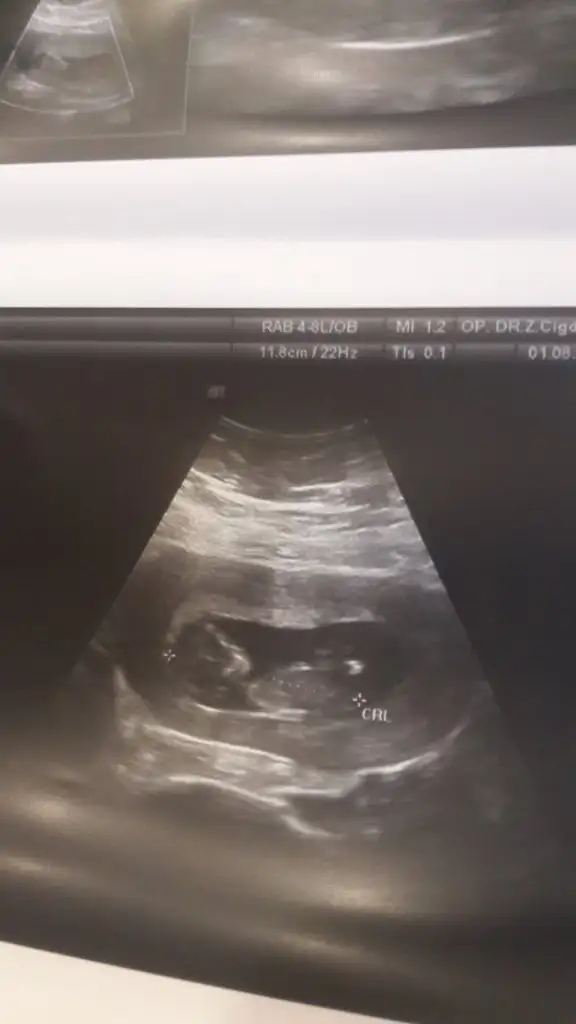

Erkek gibi kafa sekline yorumluyorum nub artık olmaz 13 hafta sanırımArkadaşlar daha önce yorum yapmıştınız ama doktor kesin bişey söylemiyor bunada bakabilir misiniz

Evet teşekkür ederimmmErkek gibi kafa sekline yorumluyorum nub artık olmaz 13 hafta sanırım

Tam dik degil ama ben tahminimi Erkek gibi yorumluyorum